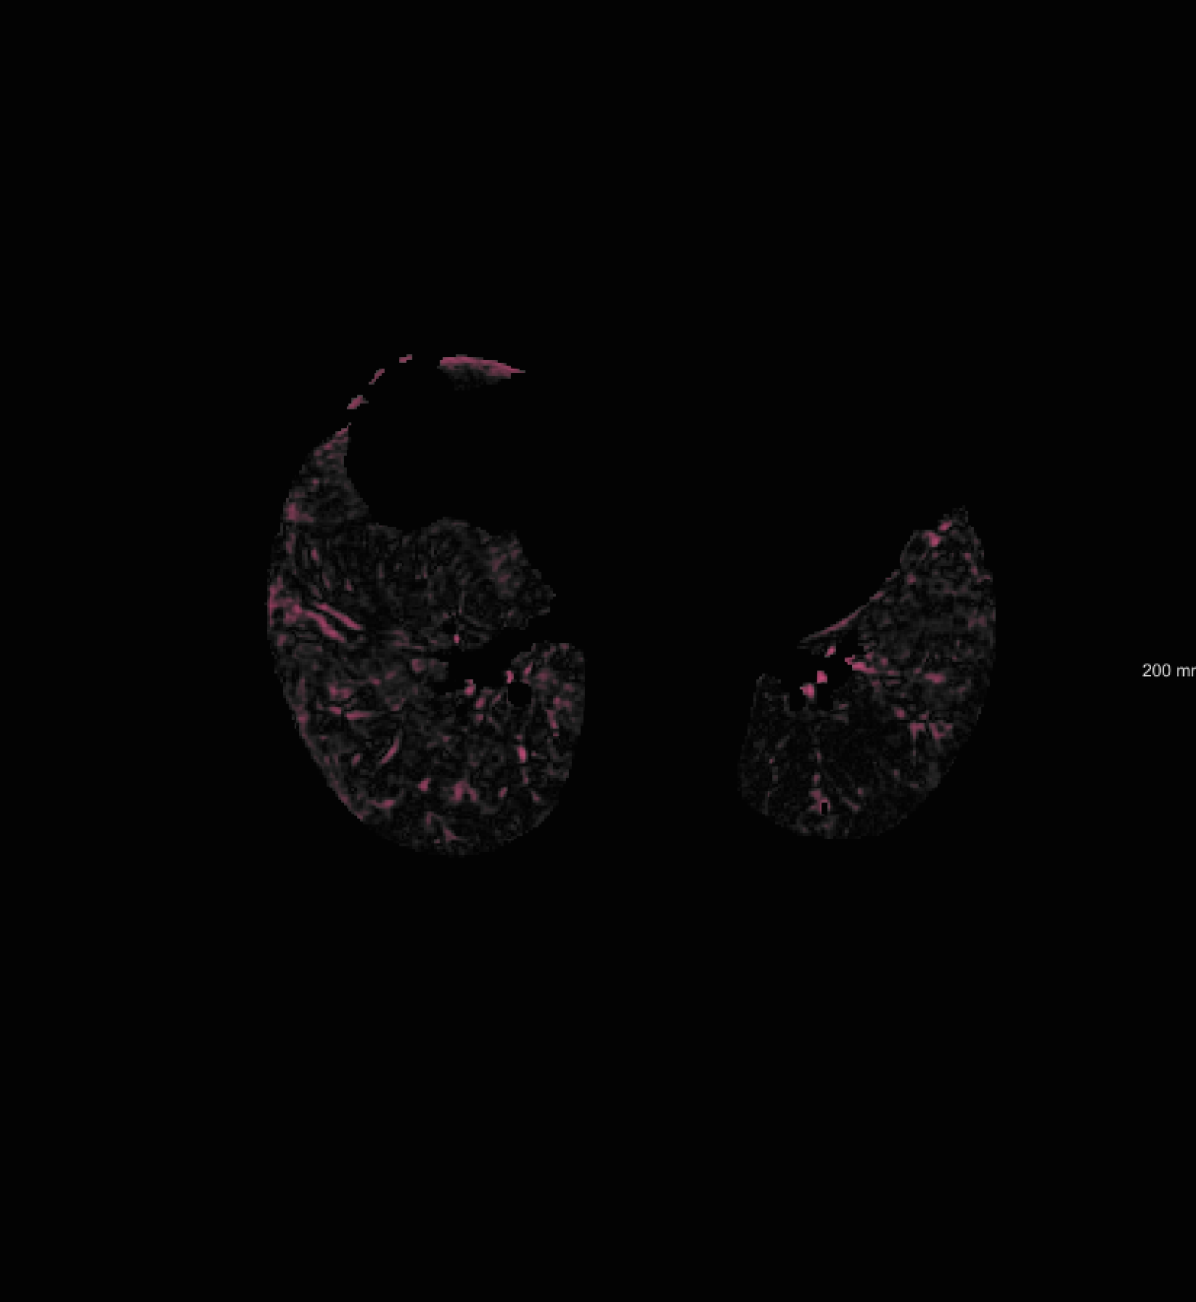

For the DIR-Lab-4DCT database, a comparison between RegNet and affine, B-spline (three resolutions), an advanced conventional registration method using sliding motion (Berendsen et al., 2014) and three other CNN-based methods (Eppenhof and Pluim, 2018; de Vos et al., 2019; Sentker et al., 2018) is available in Table IV. It can be seen that training with “S+M” improved performance slightly with respect to just “S”. Adding the respiratory motion category improved performance substantially, as these are inhale-exhale pairs; this is predominantly caused by the patients where the TRE after affine registration was still quite large. An example visualization is also available in Fig. 5(f), showing that adding the respiratory motion category can align images better in the diaphragm region. The advanced conventional registration method that leverages sliding motion (Berendsen et al., 2014) is still better than RegNet. Note that RegNet was not trained on the DIR-Lab-4DCT data, similar to Eppenhof and Pluim (2018); Sentker et al. (2018). However, de Vos et al. (2019) and Eppenhof and Pluim (2018)-DIR methods were trained on the same database but using cross-validation to report the results. Also note that the results reported in Sentker et al. (2018) are averaged over all phases of DIR-Lab-4DCT (T00 to T10), while the results of other CNN methods (including RegNet) are reported between the maximum inhale and maximum exhale phase (T00 and T50). These reported results are therefore likely somewhat better than the results for T00 and T50 only.

respiratory motion: We simulate respiratory motion with three components similar to Hub et al. (2009) as follows: Expansion of the chest in the transversal plane with a maximum scaling factor of 1.12; Transition of the diaphragm in cranio-caudal direction with a maximum deformation of ; Random deformation using the single frequency method. In order to locate the diaphragm, an automatically detected lung mask is used.